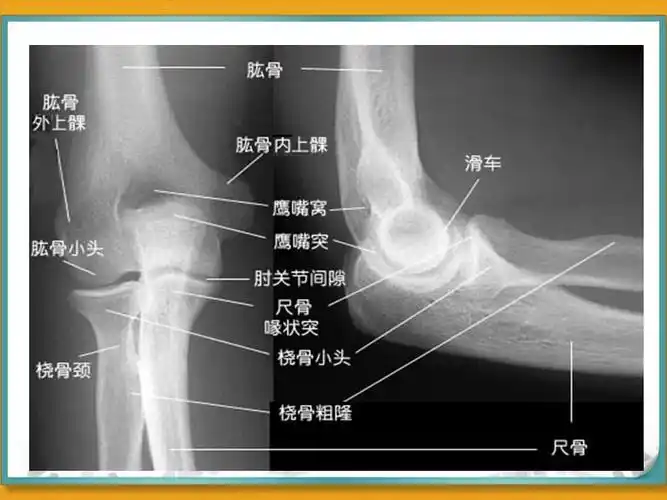

肘部局部解剖ppt

肘关节的x线常用测量及诊断分析